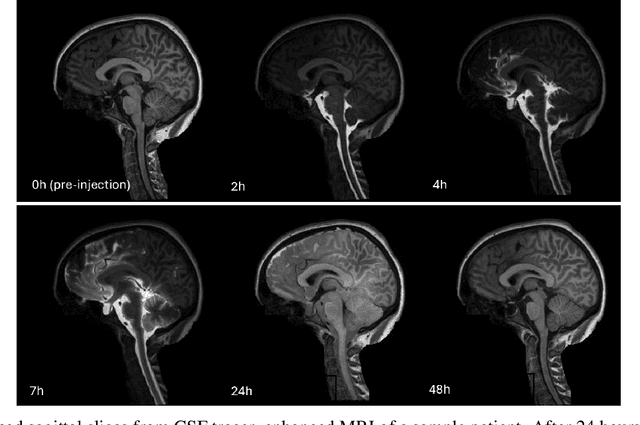

Abstract:Previous work shows evidence that cerebrospinal fluid (CSF) plays a crucial role in brain waste clearance processes, and that altered flow patterns are associated with various diseases of the central nervous system. In this study, we investigate the potential of deep learning to predict the distribution in human brain of a gadolinium-based CSF contrast agent (tracer) administered intrathecal. For this, T1-weighted magnetic resonance imaging (MRI) scans taken at multiple time points before and after intrathecal injection were utilized. We propose a U-net-based supervised learning model to predict pixel-wise signal increases at their peak after 24 hours. Its performance is evaluated based on different tracer distribution stages provided during training, including predictions from baseline scans taken before injection. Our findings indicate that using imaging data from just the first two hours post-injection for training yields tracer flow predictions comparable to those trained with additional later-stage scans. The model was further validated by comparing ventricular reflux gradings provided by neuroradiologists, and inter-rater grading among medical experts and the model showed excellent agreement. Our results demonstrate the potential of deep learning-based methods for CSF flow prediction, suggesting that fewer MRI scans could be sufficient for clinical analysis, which might significantly improve clinical efficiency, patient well-being, and lower healthcare costs.